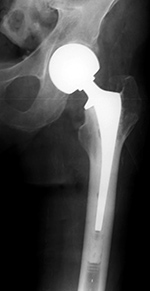

Revision total hip prosthesis |

The revision prosthesis was placed because of an earlier periprosthetic fracture. There are two cable wires proximally and two cerclage wires distally. |